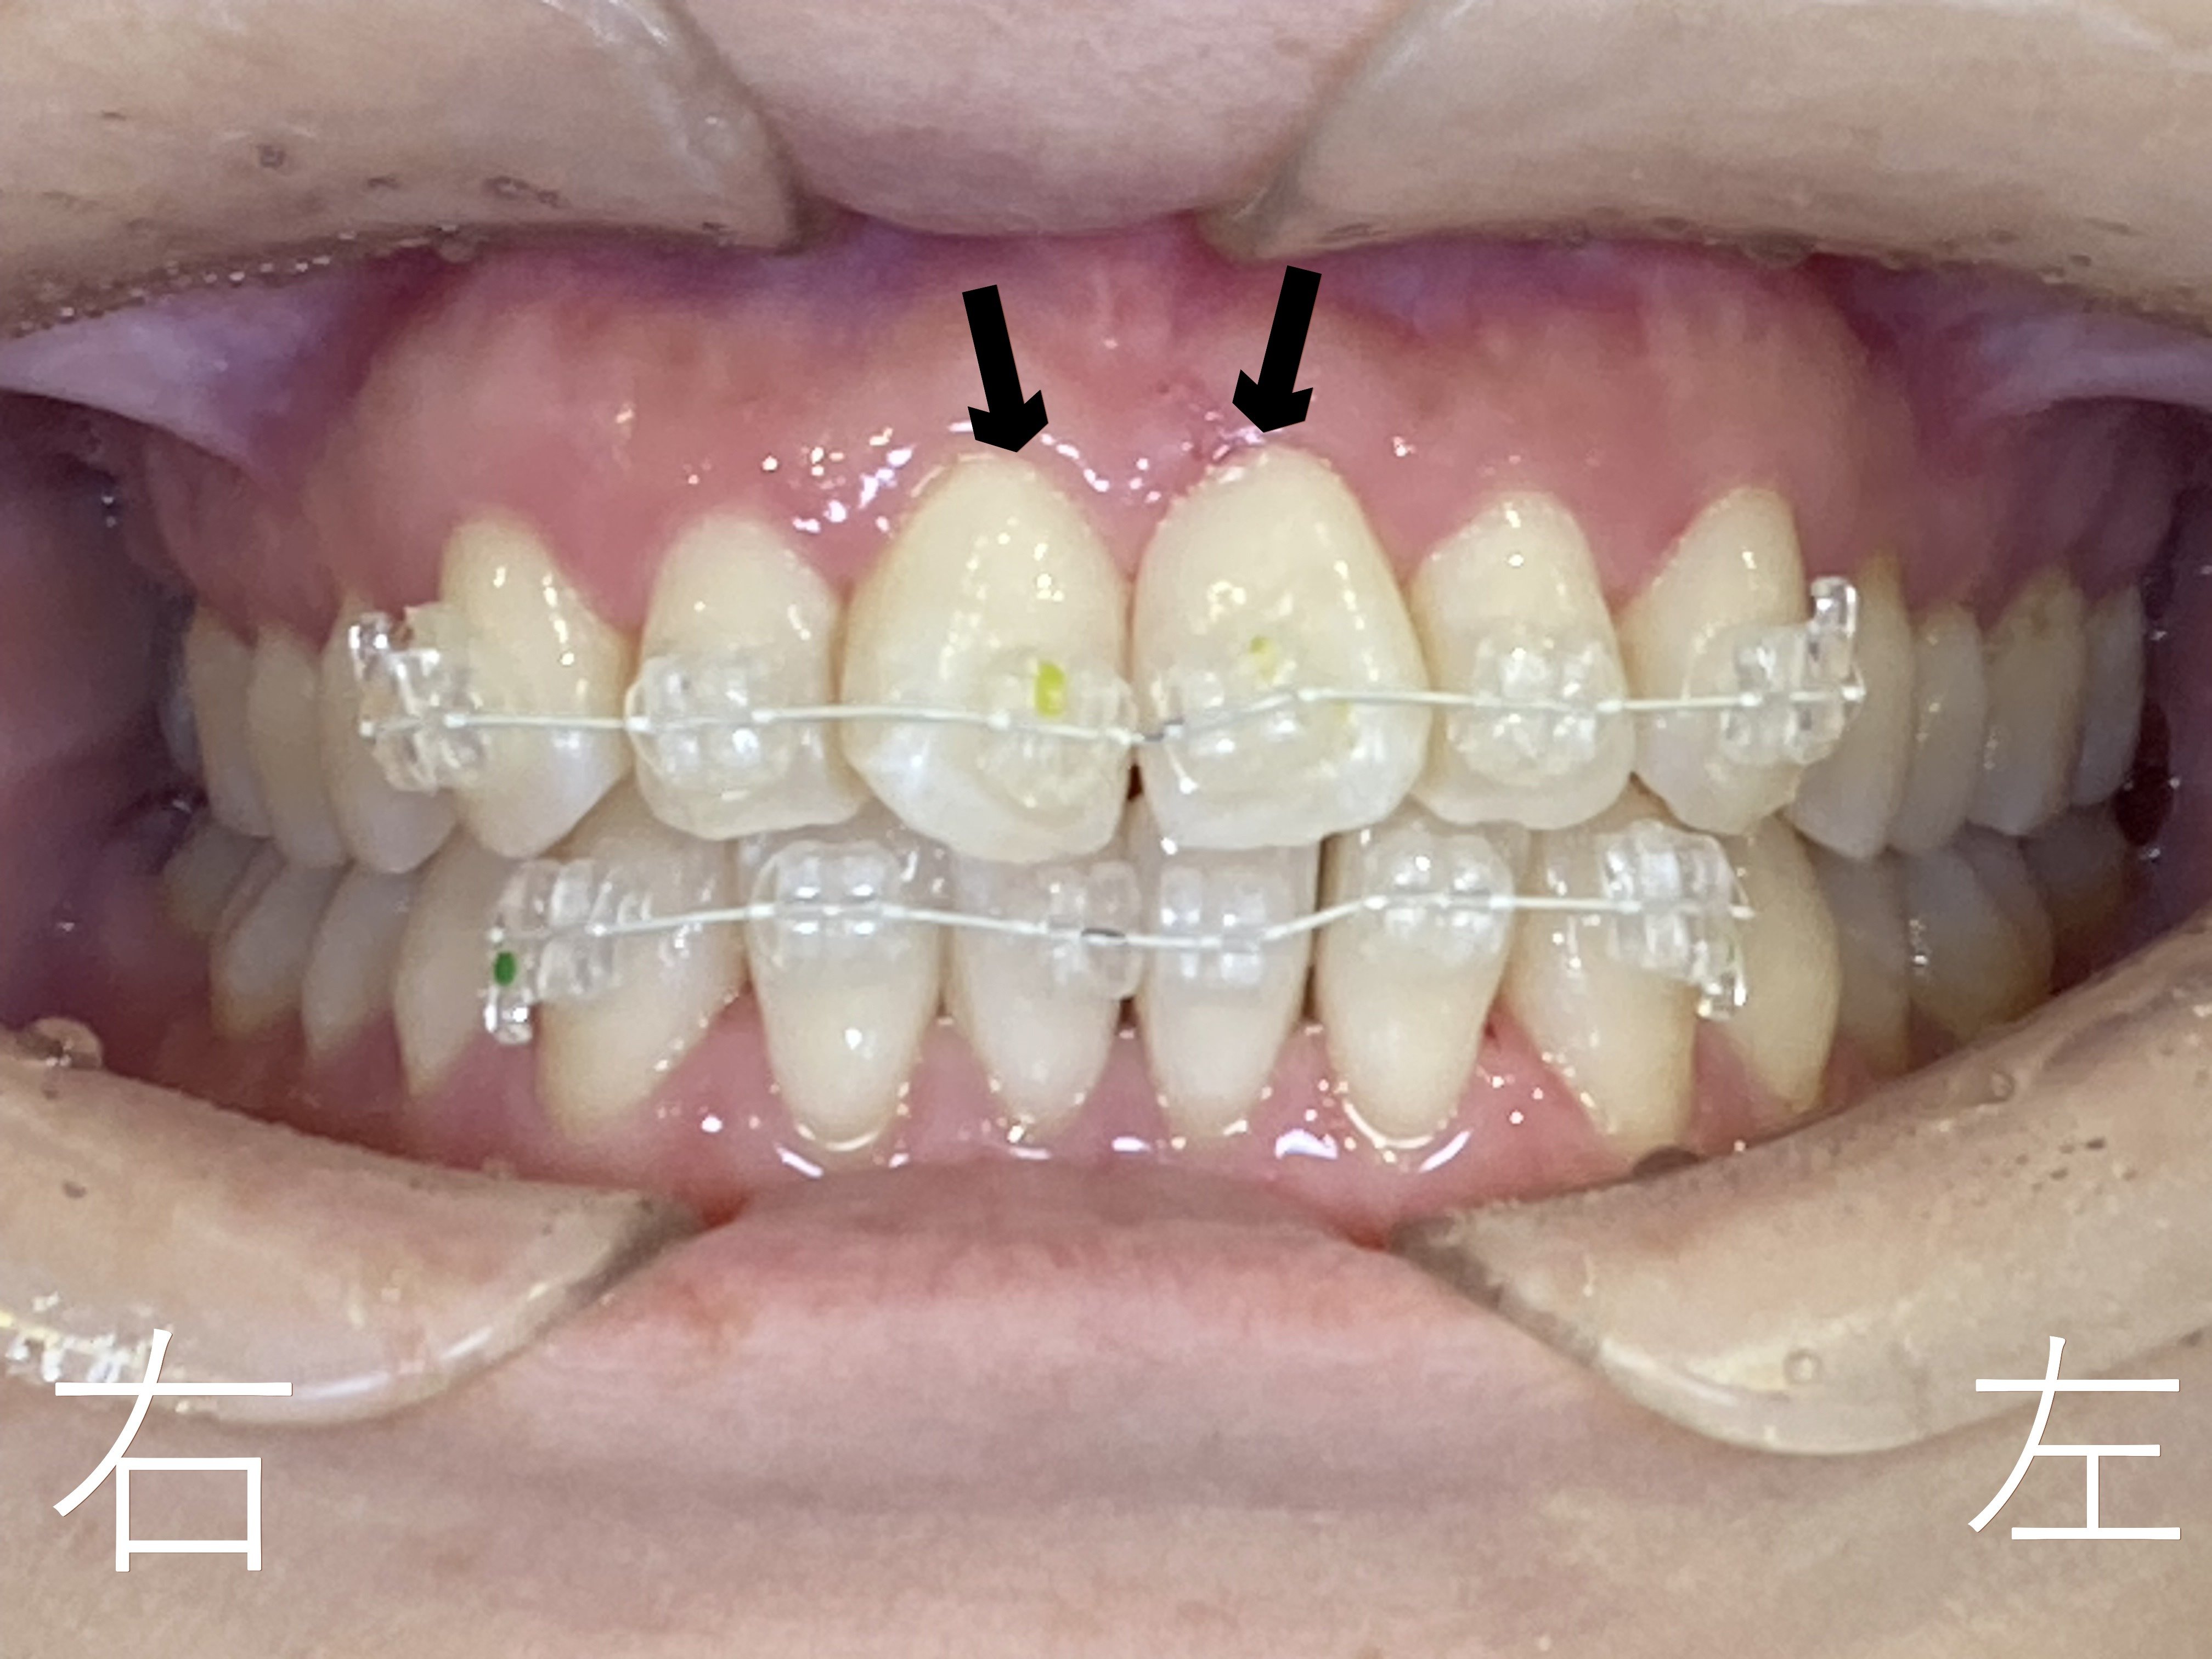

上記は上下ともセラミック製のブラケット(ボタン)を装着した正面観です。